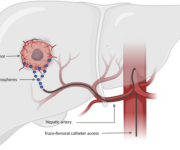

Il razionale biologico della radioembolizzazione si fonda su una peculiarità anatomica del fegato: la sua duplice vascolarizzazione. Mentre il parenchima epatico sano riceve oltre l’80% del suo apporto ematico dalla vena porta, i tumori con diametro superiore ai 2 cm dipendono per oltre l’80% dall’arteria epatica. Questa ipervascolarizzazione arteriosa delle neoplasie consente di veicolare microsfere radioattive direttamente nel letto vascolare tumorale attraverso l’arteria epatica, ottenendo un targeting selettivo che massimizza l’effetto terapeutico sulle lesioni e minimizza l’esposizione del tessuto sano circostante.

Imaging peri-procedurale e scintigrafia con 99mTc-MAA

Questa fase combina la valutazione angiografica con una simulazione della distribuzione delle microsfere.

- Angiografia: gli obiettivi principali sono:

- valutare l’anatomia vascolare arteriosa del fegato;

- verificare la pervietà della vena porta;

- identificare vasi anomali o shunt artero-venosi o gastrointestinali che potrebbero causare un’embolizzazione non-target;